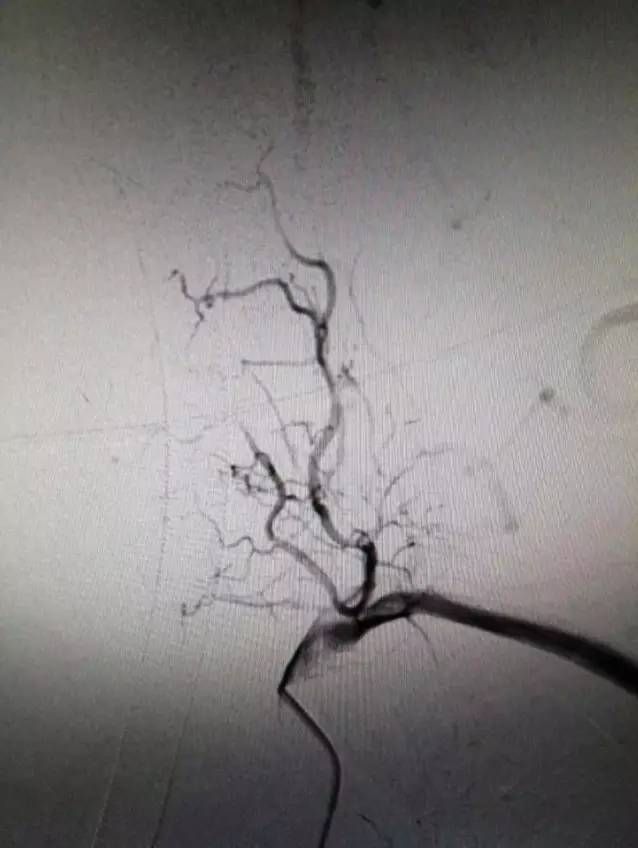

接到会诊通知,结合患者症状考虑椎基底动脉病变,未静脉溶栓直接进导管室造影,结果如下。

▼左锁骨下动脉造影显示左椎动脉闭塞,椎动脉V3段通过肌支代偿见返流。